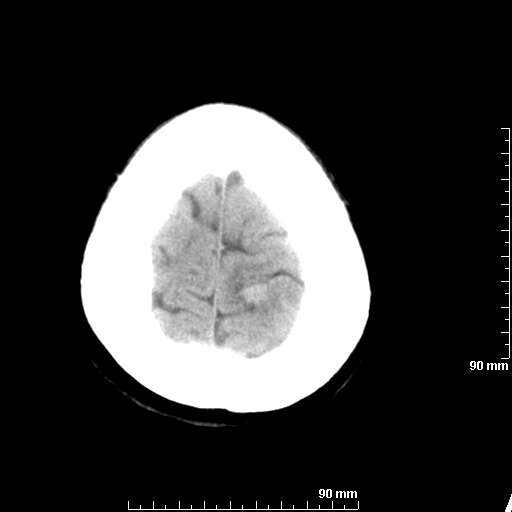

[维修案例解析] 大家猜猜看,这个伪影是怎样产生的.

二马日王 显示全部楼层 发表于 2011-6-9 18:12:55 |阅读模式

我院西门子单排CT由于一零件受损而产生的伪影.

哈哈,都不是。是虑线器fiter裂损。大家没想到吧。

哦,跟脑出血有点像哦

形状不规则,边缘模糊。比较特殊的一种伪影哈!

这种伪影很常见!伪影应该是在视野的中心的。

西门子的虑线器fiter裂损这才是很难见的问题,GE的最常见

虑线器老化,中间崩裂一块掉了

确实是虑线器,但是很少见

确实是虑线器,听说过,赞一个